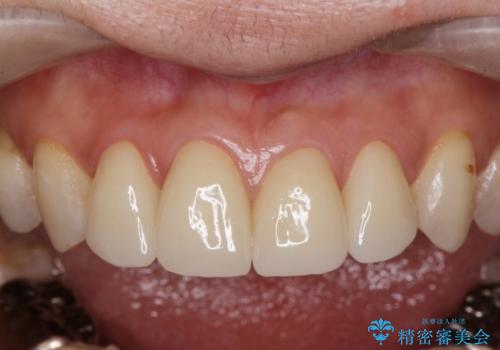

前歯の劣化したコンポジットレジン修復をセラミッククラウンへ

自然な歯の仕上がりに満足いただくことができました。